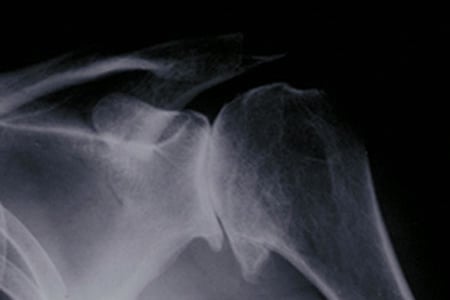

Figure 1: X-ray showing osteoarthritis of the shoulder joint, in which bones of the shoulder joint are in direct contact.

To diagnose arthritis in the shoulder, a doctor will order a series of standard X-rays. A CT scan may also be necessary to evaluate a patient's bone integrity, and magnetic resonance imaging (MRI) may be ordered to determine the condition of important surrounding soft tissues, such as the rotator cuff tendon.

In arthritis of the shoulder, this smooth cartilage degenerates, causing the bones surfaces to come into direct contact. This increases friction, which then damages and roughens the bone, causing stiffness and pain. Surgically implanted artificial replacement surfaces restore pain-free movement, strength and function.